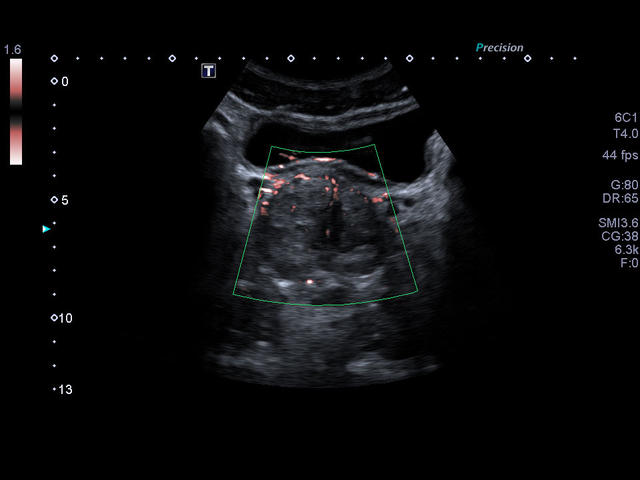

Xario 200 — это продуманная эргономика, впечатляющее качество изображения, отлаженный рабочий процесс и предельно высокая компактность. В Xario 200 цветовая доплеровская визуализация вышла на качественно новый уровень. Полностью интегрированная система управления данными пациентов и изображениями системы Xario обеспечивает удобный просмотр и простое управление исследованиями.

- Цветной, энергетический допплер - Colour Doppler Imaging/ Color Angio (CDI/CA).

- Одновременная обработка множества смежных ультразвуковых линий Precision Imaging